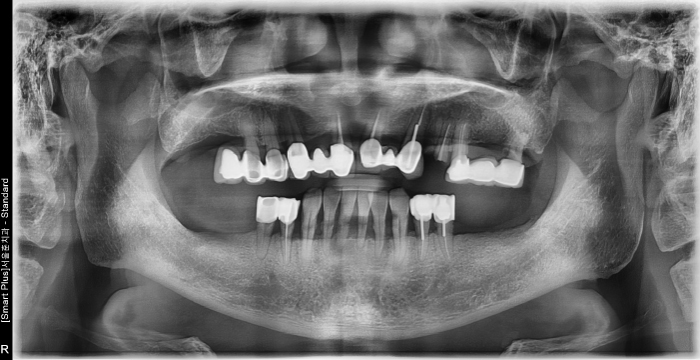

즉시 식립 임플란트 전후 사례

• 식립 전

식립 후

진단 / 3차원 CT / T-Scan교합 분석

서울바른훈치과는 임플란트 전문의 서울대 출신 이상훈 대표원장님이 직접 상담합니다. 3차원 CT분석으로 임플란트 식립 부위의 각도를 파악, 정확한 뼈의 상태를 진단합니다. T-Scan(교합분석장비)를 통해 치아와 치아 사이의 0.01mm의 미세한 오차를 분석합니다.